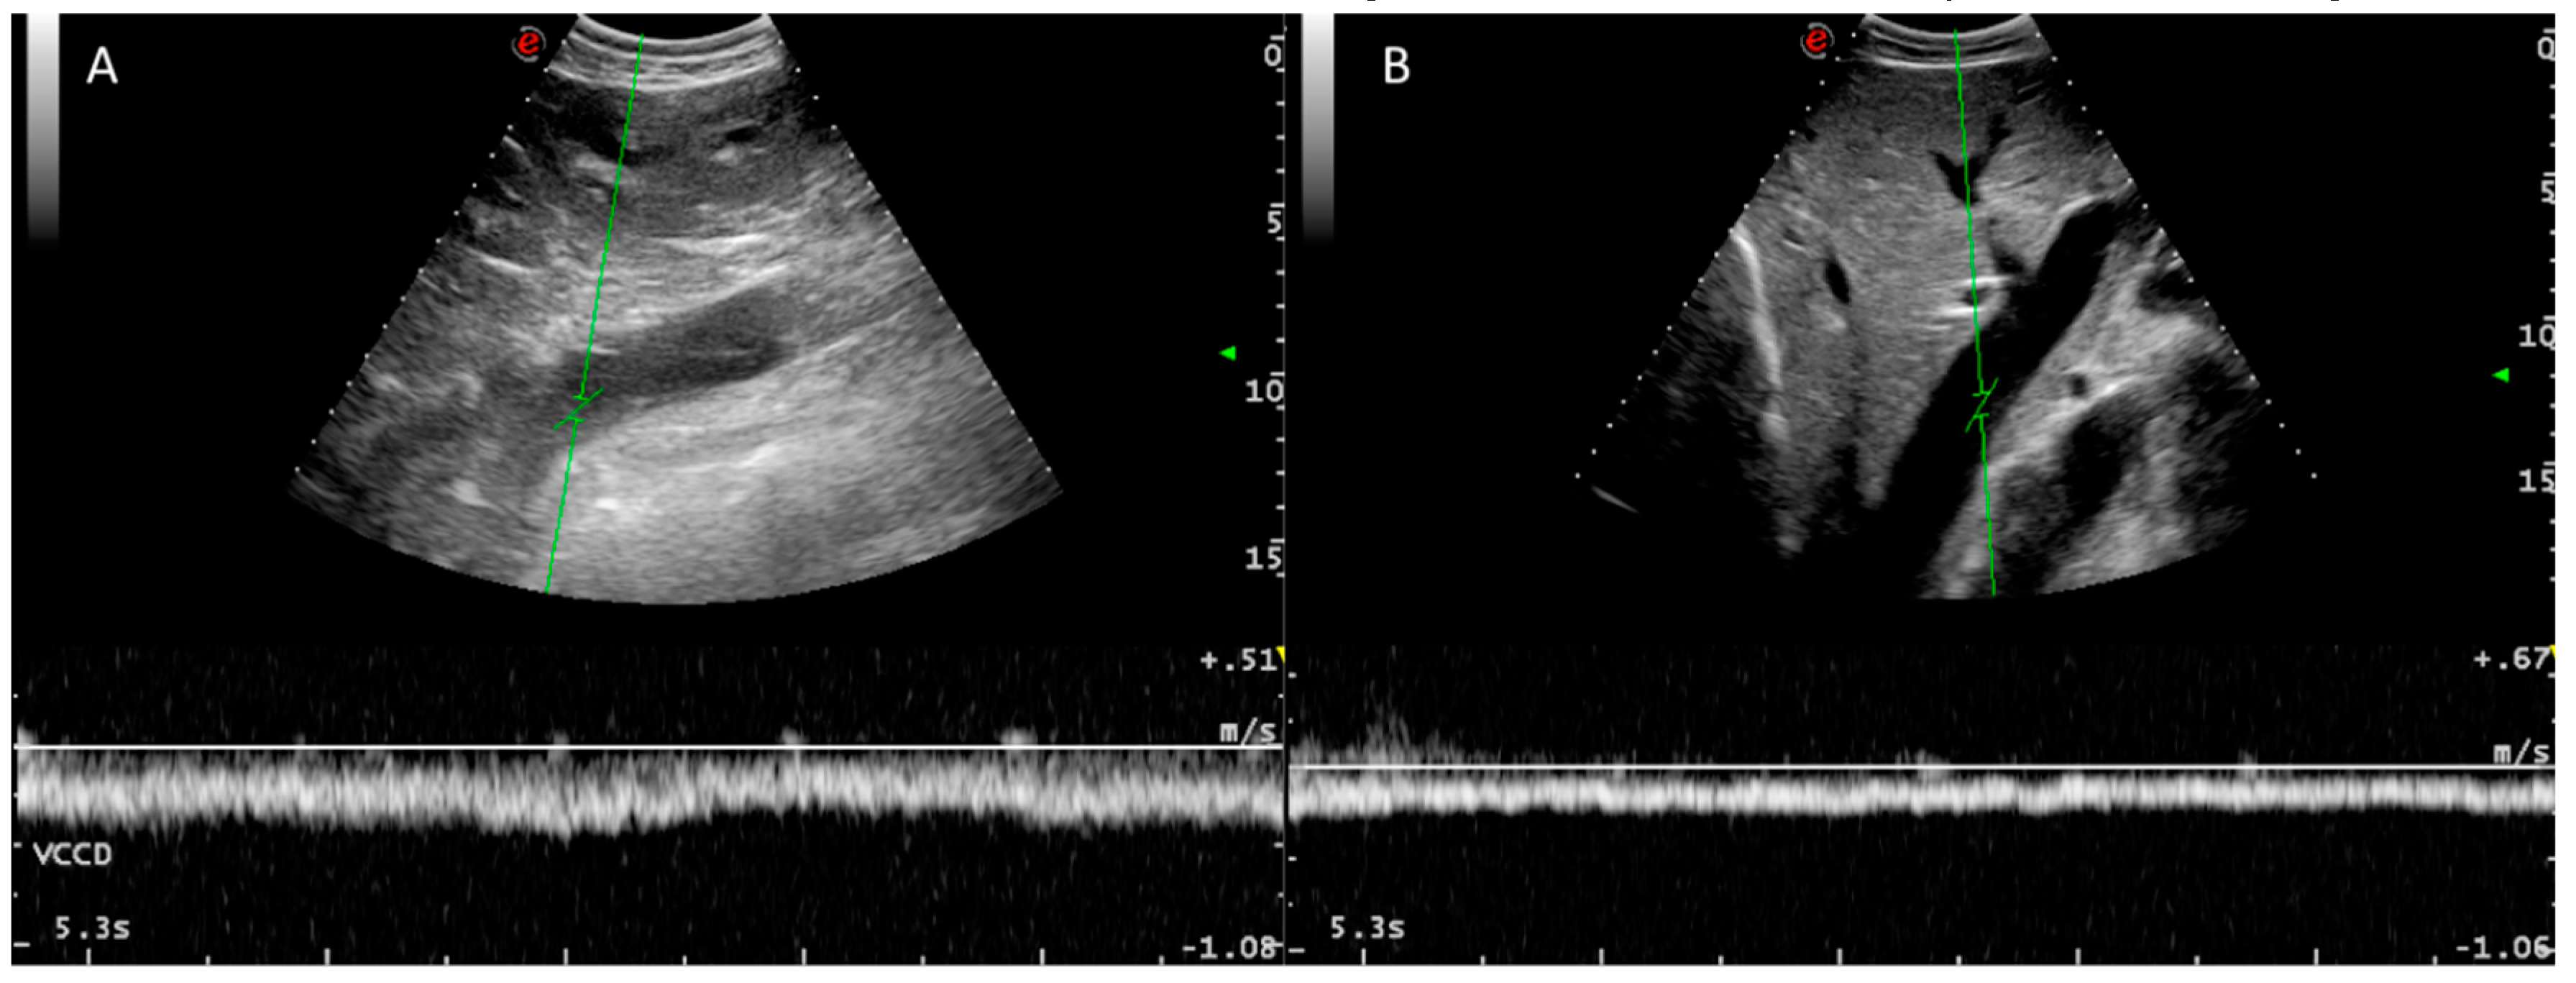

3.3. Caudal Vena Cava and Hepatic Veins